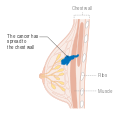

يمكن أن تؤدي الأورام الخبيثة إلى أورام نقيلية - أورام ثانوية (تنشأ من الورم الرئيسي) تنتشر إلى ما بعد مكان نشأتها. تعتمد الأعراض التي يسببها سرطان الثدي النقيلي على موقع الورم الخبيث. تشمل المواقع الشائعة للورم الخبيث العظام والكبد والرئة والمخ.[34] عندما يصل السرطان إلى مثل هذه الحالة الغازية، يتم تصنيفه على أنه سرطان من المرحلة الرابعة، وغالبًا ما تكون سرطانات هذه الحالة قاتلة.[35] تشمل الأعراض الشائعة لسرطان المرحلة الرابعة فقدان الوزن غير المبرر وآلام العظام والمفاصل واليرقان والأعراض العصبية. تسمى هذه الأعراض أعراض غير محددة لأنها يمكن أن تكون مظاهر لأمراض أخرى كثيرة.[36] نادرًا ما ينتشر سرطان الثدي إلى مواقع غير شائعة جدًا مثل العقد الليمفاوية المحيطة بالبنكرياس مما يؤدي إلى انسداد القنوات الصفراوية مما يؤدي إلى صعوبات في التشخيص.[37]

- المرحلة: مراحل سرطان الثدي باستخدام نظام TNM يعتمد على حجم tumor (T) "الورم" سواء أكان أم لم يكن منتشراً إلى العقد nodes (N) اللمفاوية تحت الإبط، أو كان الورم metastasized (M) "منتشراً" (أي منتشر لأكثر من مكان في الجسم). حجم أكبر، انتشار عقدي، والورم الخبيث له رقم مرحلة أكبر ومآل أسوأ.

- المرحلة 4: هو السرطان "النقيلي" الذي له مآل أقل مواتاة لانتشاره خارج الثدي والغدد الليمفاوية الإقليمية.